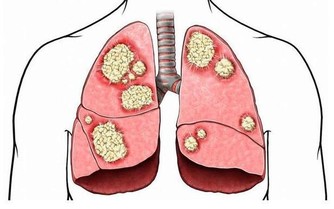

這是由於肝臟本身就有強大的代謝功能,肝癌的表現多種多樣,容易被忽視。肝位於上腹部,肝癌初期並無徵兆,一般人難以察覺,甚至當腫瘤增大至十公分以上時,有的人還是缺乏典型症狀。

當肝臟腫瘤逐步增大,有可能會壓迫附近的橫膈膜,亦可壓著肺部以下的肌肉神經。而這些被壓著的神經正好是連接右肩的神經,就會引發右肩疼痛。所以,當出現反反复复的右肩膀疼痛時,經過適當的治療,症狀未能好轉,要及時檢查肝臟以排除存在的病變。